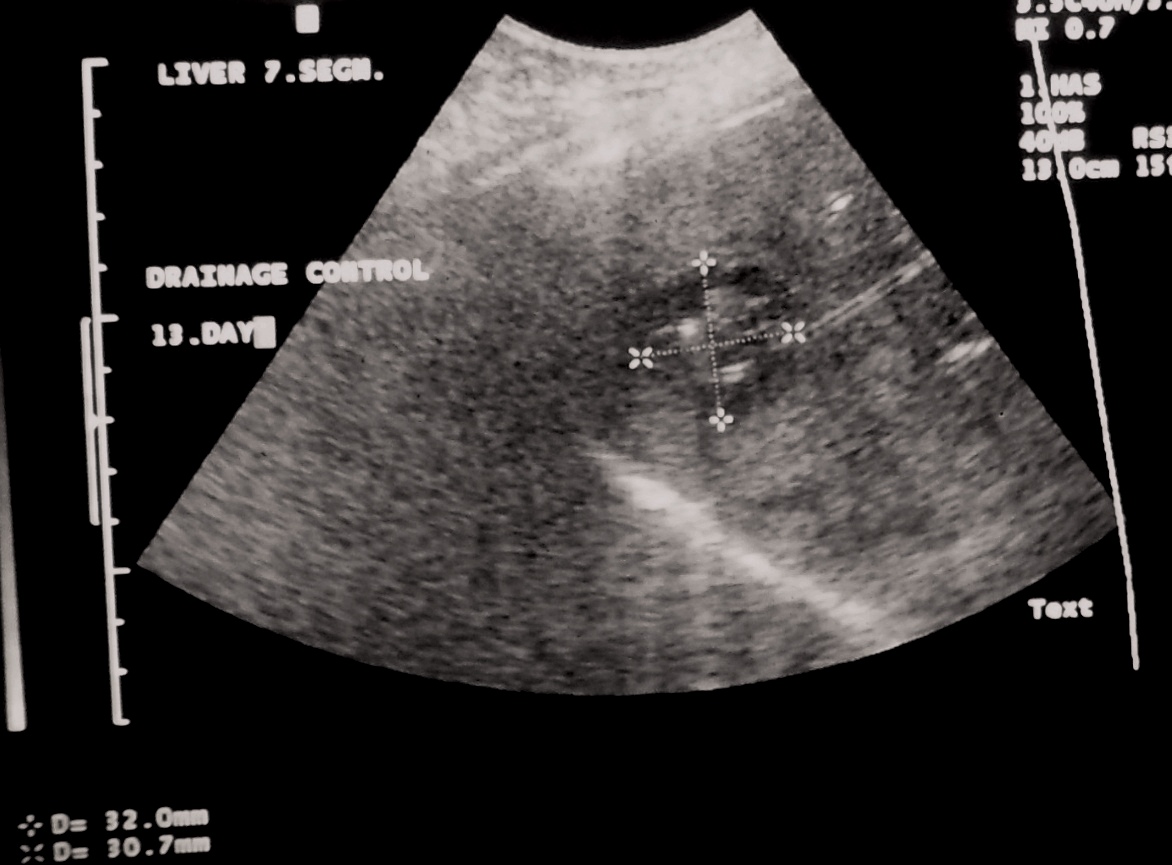

Abscess healing can be accelerated by repeated drainage and lavage of the contents of the abscess. (Figure 11.)

Image

Figure 10. – Hepatic cyst before alcoholic sclerotization, cyst is filled with diluted contrast material.

Figure 11. – US guided hepatic abscess drainage control (day 13, after several rounds of lavage and cleaning of the abscess)

The length of the percutaneous drainage is influenced by the washout of the contents and the reduction of its size.